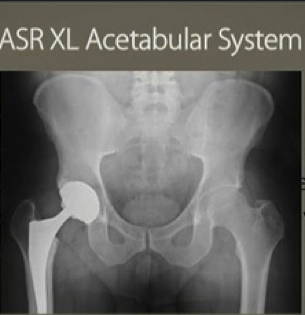

Three years before Johnson & Johnson’s DePuy unit recalled its chromium and cobalt hip implants, company marketers feared the backlash over metal ion debris in patients, a jury in Los Angeles was told.

A DePuy marketing executive, Randall Kilburn, testified today in California state court at the first of 10,000 lawsuits to go to trial over the ASR hips, which J&J withdrew in August 2010 when their failure rate reached 12 percent. Kilburn was asked about a meeting in July 2007 in Chicago, where the marketing team discussed several hip devices.

Jurors are weighing the lawsuit of Loren Kransky, 65, who claims the ASR hip was defectively designed and the company failed to warn of risks. Kransky’s lawsuit and many others claim that the shallow design of the hip cup, in which a metal ball sitting atop the femur rotates, led to the shedding of metal ions in surrounding tissue and bloodstream.

That device advanced metal-on-metal designs of the 1960s and 1970s that had fallen out of favor as metal-on-polyethylene grew popular. DePuy began selling a similar device, the ASR Hip Resurfacing System, outside the U.S. in 2003. Both devices used an alloy of cobalt and chromium.